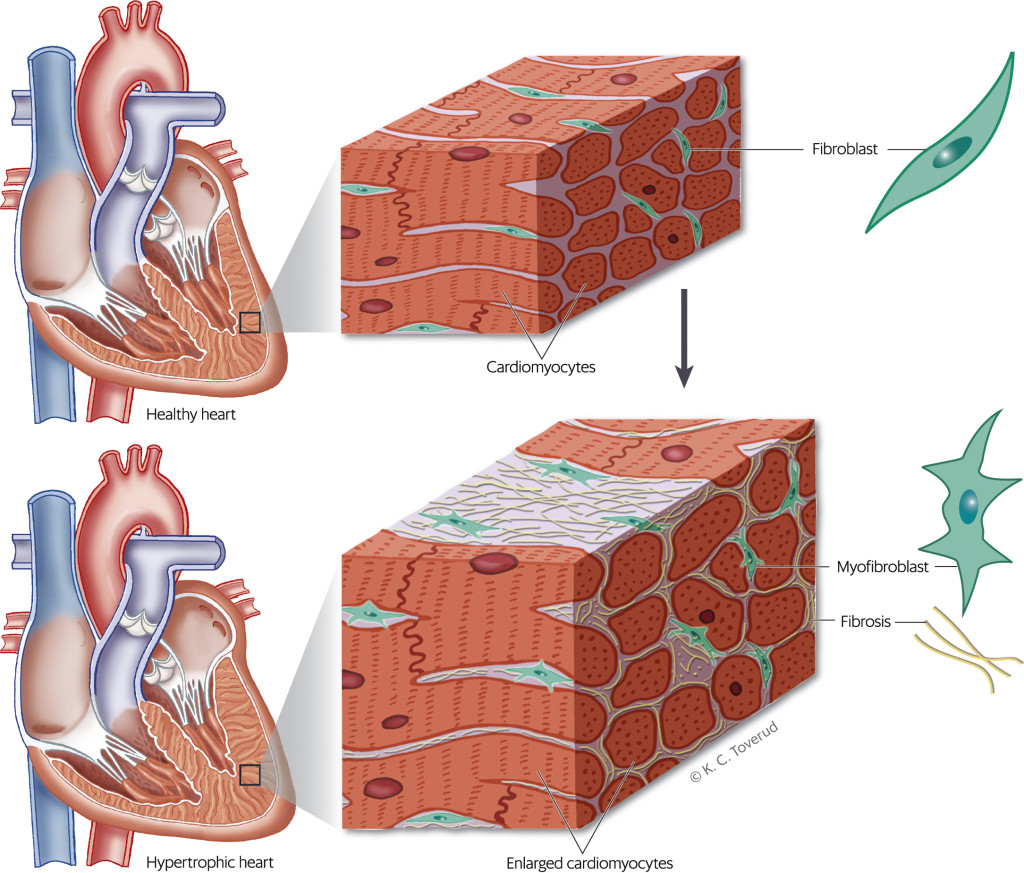

When cardiac damage and stress occur, various substances cause fibroblasts to become activated and transdifferentiate into myofibroblasts (2)−(7) (Figure 2) (8). The myofibroblasts increase the production of proteins that are deposited in the extracellular matrix (2–5). Collagen I, which accounts for about 80 % of the collagen in the myocardium, makes the myocardium stiffer and increases most in myocardial fibrosis (7, 9, 10). Cross-linking makes the collagen matrix stiffer and more difficult to break down with proteinases (2, 3, 5, 11). Fibrosis occurs as a result of net collagen production. Fibrosis restricts the supply of oxygen and nourishment to the myocardium (2, 3). Myocardial fibrosis causes electrical and structural changes that predispose patients to arrhythmias, heart failure and ischaemia (12). Figure 3 summarises the pathophysiology and consequences of myocardial fibrosis.